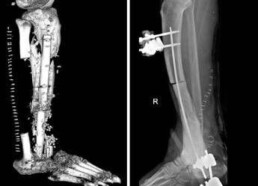

Batterio gli 'mangia' la carne, operazione al Gemelli gli salva gamba e piede

(Adnkronos) - Un mix di batteri 'mangia-carne' lo aveva infettato dopo una banale ferita cutanea, consumandogli buona parte di una gamba fino alla caviglia. Onya (nome di fantasia) è stato a un passo da perdere l'arto, il piede e la vita stessa, pericolo scongiurato grazie a un complesso intervento eseguito da un team di ortopedici e chirurghi palastici al Policlinico Gemelli di Roma.

I medici hanno ricostruito al giovane, di origini nigeriane, intere parti di ossa, muscoli e pelle. Le operazioni hanno avuto successo. A distanza di 1 mese Onya cammina con le stampelle e vive in una casa famiglia, assistito dai servizi sociali. Emigrato dalla Nigeria e approdato sulle coste della Calabria nel 2017, Onya è stato accolto in Italia e dopo qualche mese gli è stato offerto un lavoro da operatore ecologico in una città del Lazio, raccontano dal Gemelli. L'inizio di una nuova vita, spezzata sul nascere da un incidente. Mentre andava a lavorare, il giovane finisce con la gamba destra dentro una buca coperta da un compensato di legno e riporta una brutta ferita. Per lui inizia un'odissea tra vari ospedali: visite, interventi parziali e tanti antibiotici, finché Onya arriva al Pronto soccorso del Gemelli. La diagnosi è di osteomielite post-traumatica, una grave infezione ossea che coinvolgeva gran parte della tibia e della caviglia della gamba destra, contratta a seguito di quel trauma iniziale apparentemente banale e causata - come rileveranno i tamponi colturali profondi - da una serie di batteri mangia-carne (flesh-eating): dallo Stafilococco aureus all'Escherichia coli, passando per tanti altri, che in pochi mesi avevano devastato la cute e i muscoli del giovane, fino a intaccare l'osso. In casi come questi gli antibiotici non bastano più, serve la chirurgia per rimuovere le parti infette e l'ampuazione e un pericolo concreto. Onya però non ne vuole sapere. I medici provano a convincerlo, ma lui è irremovibile e così l'ortopedico Carlo Perisano e la chirurga plastica Elisabetta Pataia gli propongono una soluzione alternativa: proveranno a rimuovere tutta l'infezione, che significa asportare la parte inferiore della gamba e parte della caviglia, per poi ricostruire il tutto. "Una vera e propria impresa durata circa 1 anno" con "vari interventi, mai descritta prima in letteratura - si legge in una nota - che ha restituito a Onya la sua gamba". Spiega Perisano, ricercatore in Ortopedia e Traumatologia all'Università Cattolica del Sacro Cuore e dirigente medico presso la Uoc di Ortopedia e Traumatologia della Fondazione Policlinico universitario Agostino Gemelli Irccs: "In una prima fase abbiamo resecato quasi tutta la tibia del paziente sotto il ginocchio e l'astragalo, per rimuovere tutti i focolai di infezione. Successivamente abbiamo messo un sostituto temporaneo dell'osso, cioè uno spaziatore cementato e antibiotato, al fine di far guarire i tessuti e ridurre il rischio di re-infezione. Dopo 4 mesi di terapia antibiotica, abbiamo iniziato un percorso di ricostruzione ossea". Inizialmente è stato fatto un tentativo di allungamento dell'arto con un fissatore esterno. "Si tratta di un intervento particolare - descrive l'ortopedico - consistente nell'osteotomia della parte di tibia rimanente e nella distrazione dei 2 monconi ossei (il gap osseo era di circa 20 cm), per permettere all'osso neoformato di crescere tra le porzioni di osso residue. In questo modo abbiamo recuperato 10 centimetri di osso; tanti, ma non sufficienti a ricostruire la parte mancante di tibia". E' stato quindi necessario modificare la strategia chirurgica. Per dare un'adeguata copertura cutanea e permettere all'osso sottostante di rigenerarsi e guarire, l'équipe multidisciplinare di ortopedici e chirurghi plastici ha effettuato dunque un delicato intervento, definito come "del tutto inedito". Illustra Pataia, docente di Chirurgia ortoplastica in Cattolica e chirurgo plastico nella Uoc di Ortopedia e Traumatologia del Gemelli: "Abbiamo effettuato una ricostruzione complessa prelevando 3 lembi, un muscolo-cutaneo dalla coscia e 2 ossei da entrambi i peroni del paziente. Successivamente, questa sorta di patchwork osseo-muscolo-cutaneo è stato collegato con tecnica microchirurgica. Si tratta di un sistema detto 'lembo-chimera', che consiste nel collegare un lembo muscolo-cutaneo al vaso arterioso della gamba ricevente, per poi collegare tra di loro i restanti lembi. In pratica il primo lembo alimenta l'altro, attraverso una serie di connessioni vascolari realizzate al microscopio, che partendo da un solo vaso ha consentito di alimentare 3 lembi diversi". Utilizzando infine il perone della gamba sana e quello della gamba malata, Perisano ha ricostruito la parte mancante della tibia e l'astragalo del paziente, fissando il tutto con delle viti ortopediche e mettendo a protezione un fissatore esterno circolare, per permettere la guarigione dei tessuti e far consolidare le parti ossee. "Si tratta di un intervento eccezionale - commenta Giulio Maccauro, ordinario di Ortopedia alla Cattolica e direttore della Uoc di Ortopedia e Traumatologia del Gemelli - che conferma la validità della nostra intuizione di creare un servizio di chirurgia ortoplastica, interdisciplinare con ortopedici e chirurghi plastici, all'interno della nostra struttura di Ortopedia e Traumatologia. Si tratta di una disciplina nuova, che ha pochi altri centri in Italia". ---cronacawebinfo@adnkronos.com (Web Info)